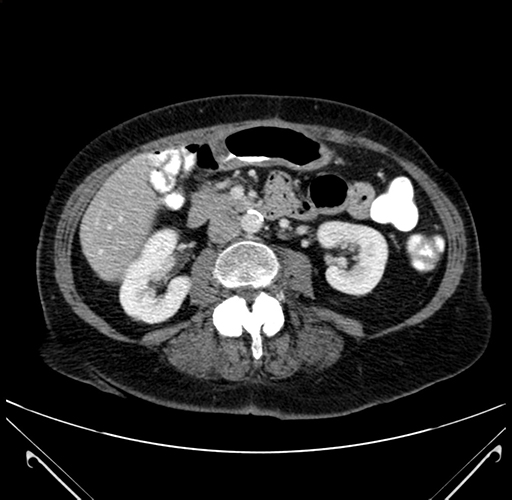

Pre-Chemo: Axial Venous

Axial Venous